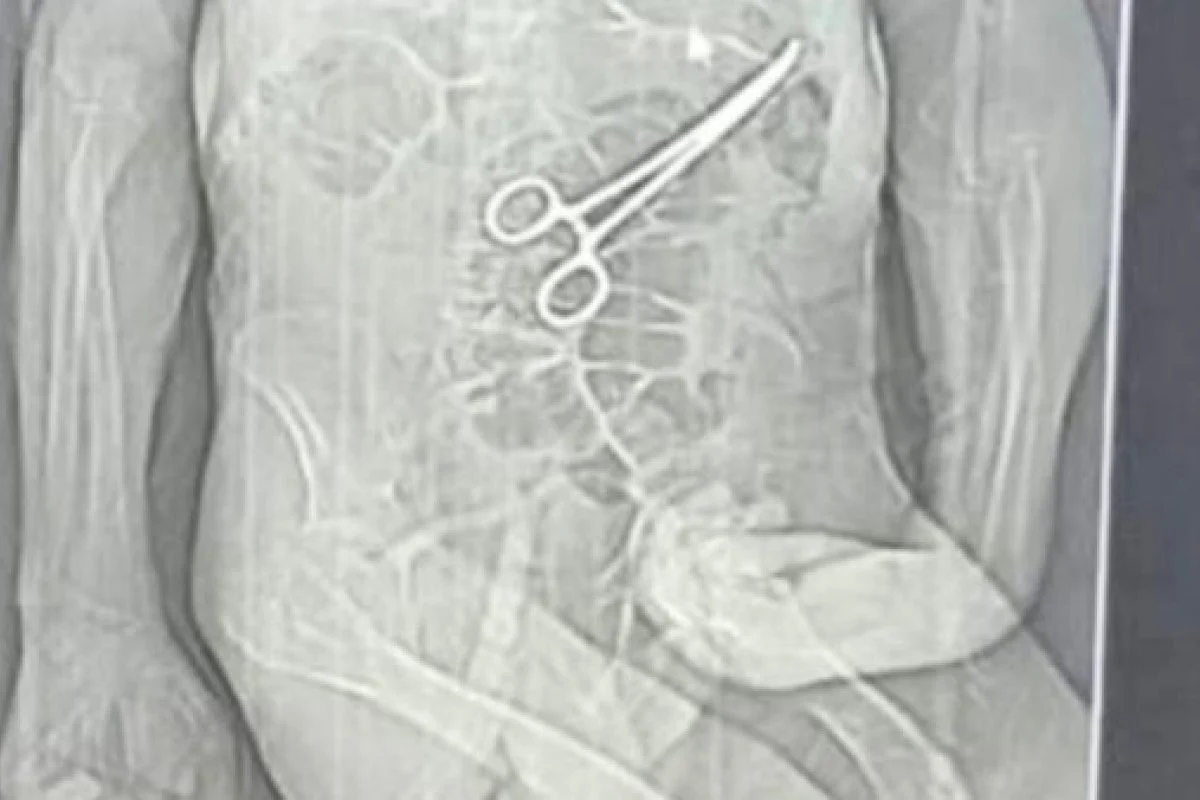

Segundo os parentes, a equipe médica não informou sobre a existência do objeto estranho identificado no abdômen do paciente. A descoberta, segundo o relato, teria ocorrido apenas após a divulgação de uma reportagem em uma rádio local, que apresentou imagens de uma tomografia indicando a pinça.

Foi nesse período que uma tomografia identificou, de acordo com a Secretaria de Saúde, “um corpo estranho na cavidade abdominal” do paciente. Diante do achado, uma nova cirurgia foi realizada em 11 de dezembro com o objetivo de remover o objeto.